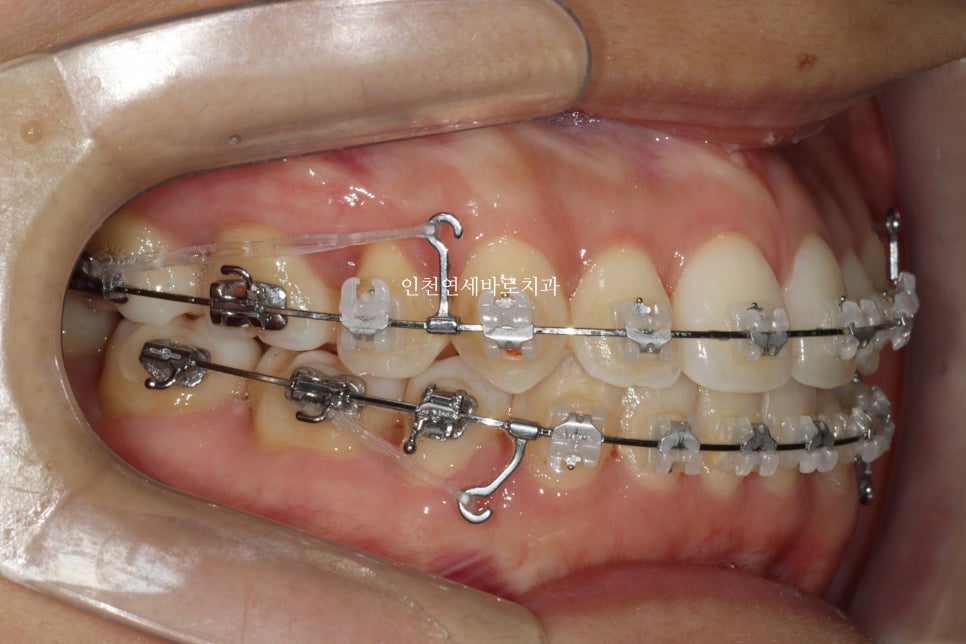

양쪽에 미니스크류 2개도 심고 중심선을 맞추기 위한 치료를 계속해나갔습니다…

그러던 중 GG

좁혀지지 않는 치아의 중심선때문에 클리피씨로 교체를 원했습니다.

원하시는 대로 클리피씨를 붙이기로 했고 ㅠ

일반 장치로 진행을 이어갔습니다. 저로서는 너무 아쉬움

그래도 일단 목표한대로 끝내야하니 계속 치료를 이어갑니다